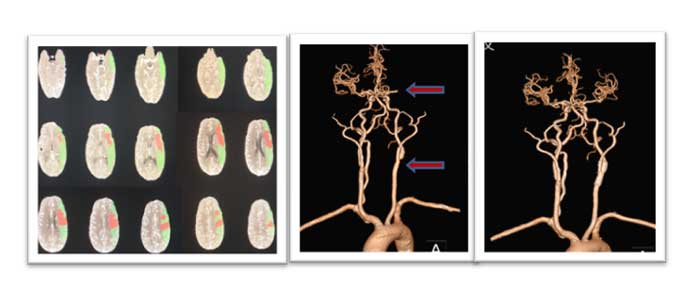

(左图)术前CTP显示:绿色区域左侧额叶、顶叶、颞叶、枕叶、小脑广泛血流灌注异常,其中红色为核心梗死。(中图)术前头颈部CTA显示:左侧大脑中近端闭塞及左侧颈内动脉起始重度狭窄,分别见红色箭头上、下。(右图)术后一个月左侧大脑中动脉闭塞已再通,颈内动脉起始狭窄支架置入术后恢复正常。

患者李某,男性,56岁,主因言语不利、右侧肢体无力、意识不清2小时20分就诊于我院急诊科,NIHSS评分26分。经我院静脉溶栓小组专家会诊,在征得家属同意后给予静脉溶栓,急诊行头颈部CTA(头颈部血管CT检查成像)及头颅CTP(头颅灌注成像)检查,提示:左侧颈总动脉远端及颈内动脉起始支架植入术后;左椎动脉重度狭窄,接近闭塞;左侧额叶、顶叶、颞叶、枕叶、小脑的血流灌注异常。患者病情危急,如不紧急处理,可能危及生命,后期还可能因大面积梗死需要行去骨瓣减压手术。为进一步挽救患者的低灌注组织,经神经外科介入小组专家会诊,征得家属同意后,在导管室为患者实施了急性血管内治疗,闭塞血管很快实现了再通,无需再行去骨瓣减压术。经抗血小板、强化降脂、改善循环、康复等治疗,患者一个月后复查影像时低灌注已消失,能够简单言语,右下肢可活动。